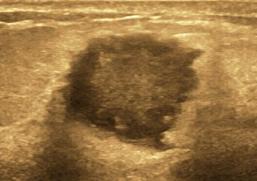

结节内回声不均,术后病理为恶性